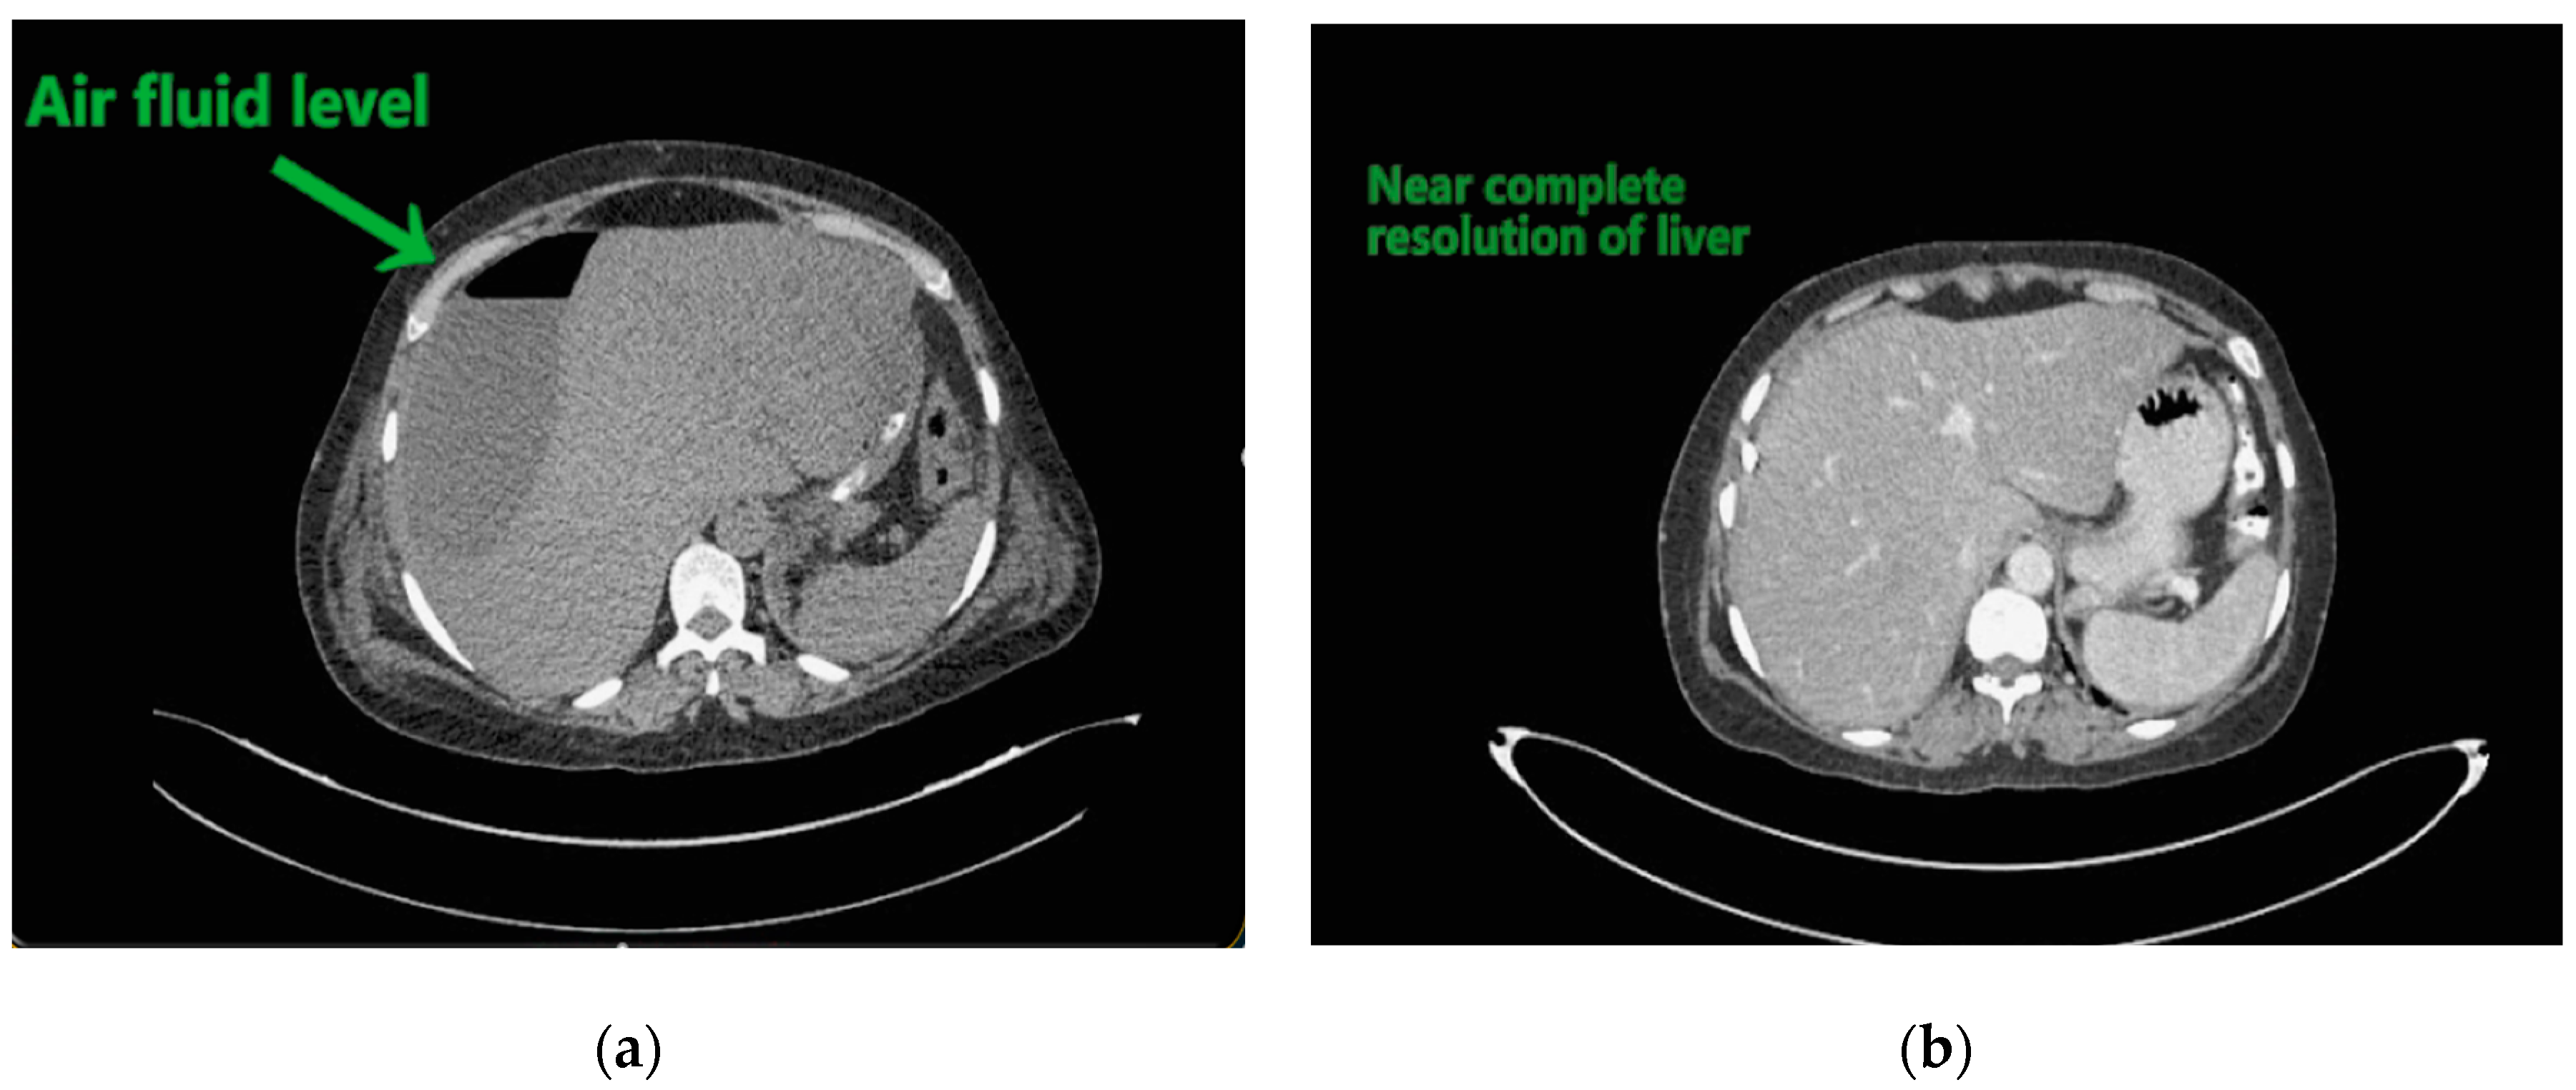

Figure 2. (a) Liver abscess showing air fluid levels; (b) showing resolution after 10 days.

Contemplating unusual location of air fluid level in an otherwise stable patient, contrast enhanced computed tomography (CECT) of the abdomen and pelvis was done. CECT was suggestive of liver abscess in segment VII, VI which was 300 cc liquified with gas formation within. The abscess had ruptured with collection tracking along the right paracolic gutter till pelvis with 800 cc liquified large collection noted within (Figure 2a and Figure 3a).

The patient underwent ultrasound guided percutaneous abscess drainage and placement of 12-Fr and 14-Fr catheter in liver and pelvic collections respectively. The aspirate was purulent and Klebsiella pneumoniae was detected in cultures. Blood culture was negative even on repeated samples. Gene xpert (CB NAAT) was negative for mycobacterium tuberculosis (MTB). Fluid samples were also negative for malignant cells. She was started on antibiotics Piperacillin and tazobactum combination and monitored for blood glucose levels as a high suspicion of diabetes. Antibiotics was switched to imipenem as per the sensitivity of fluid cultures. She was tested negative for human immunodeficiency virus (HIV). Conservative management was continued as the patient improved with a repeat CECT after 10 days showing complete resolution of liver abscess and 30–40 cc residual collection in pelvis. Her liver enzymes became normal. Drains were removed on day 12 and day 14 from liver and pelvis respectively. She developed an induration of 13 mm when tested for tuberculin skin antigen test at 72 h post inoculation suggesting positive test. Fluid adenosine deaminase (ADA) levels were found to be 250.5 U/L and patient started on category 1 anti-tubercular treatment. Patient was discharged on day 15 without sequelae.

Abdominal ultrasound, simple abdominal radiography, and other imaging techniques are useful for diagnosis, but CT is the best method for sensitive detection of gas within abscesses. In the present case X-ray showed air under right dome of Diaphragm and as patient was clinically stable, CECT was done which confirmed the diagnosis.